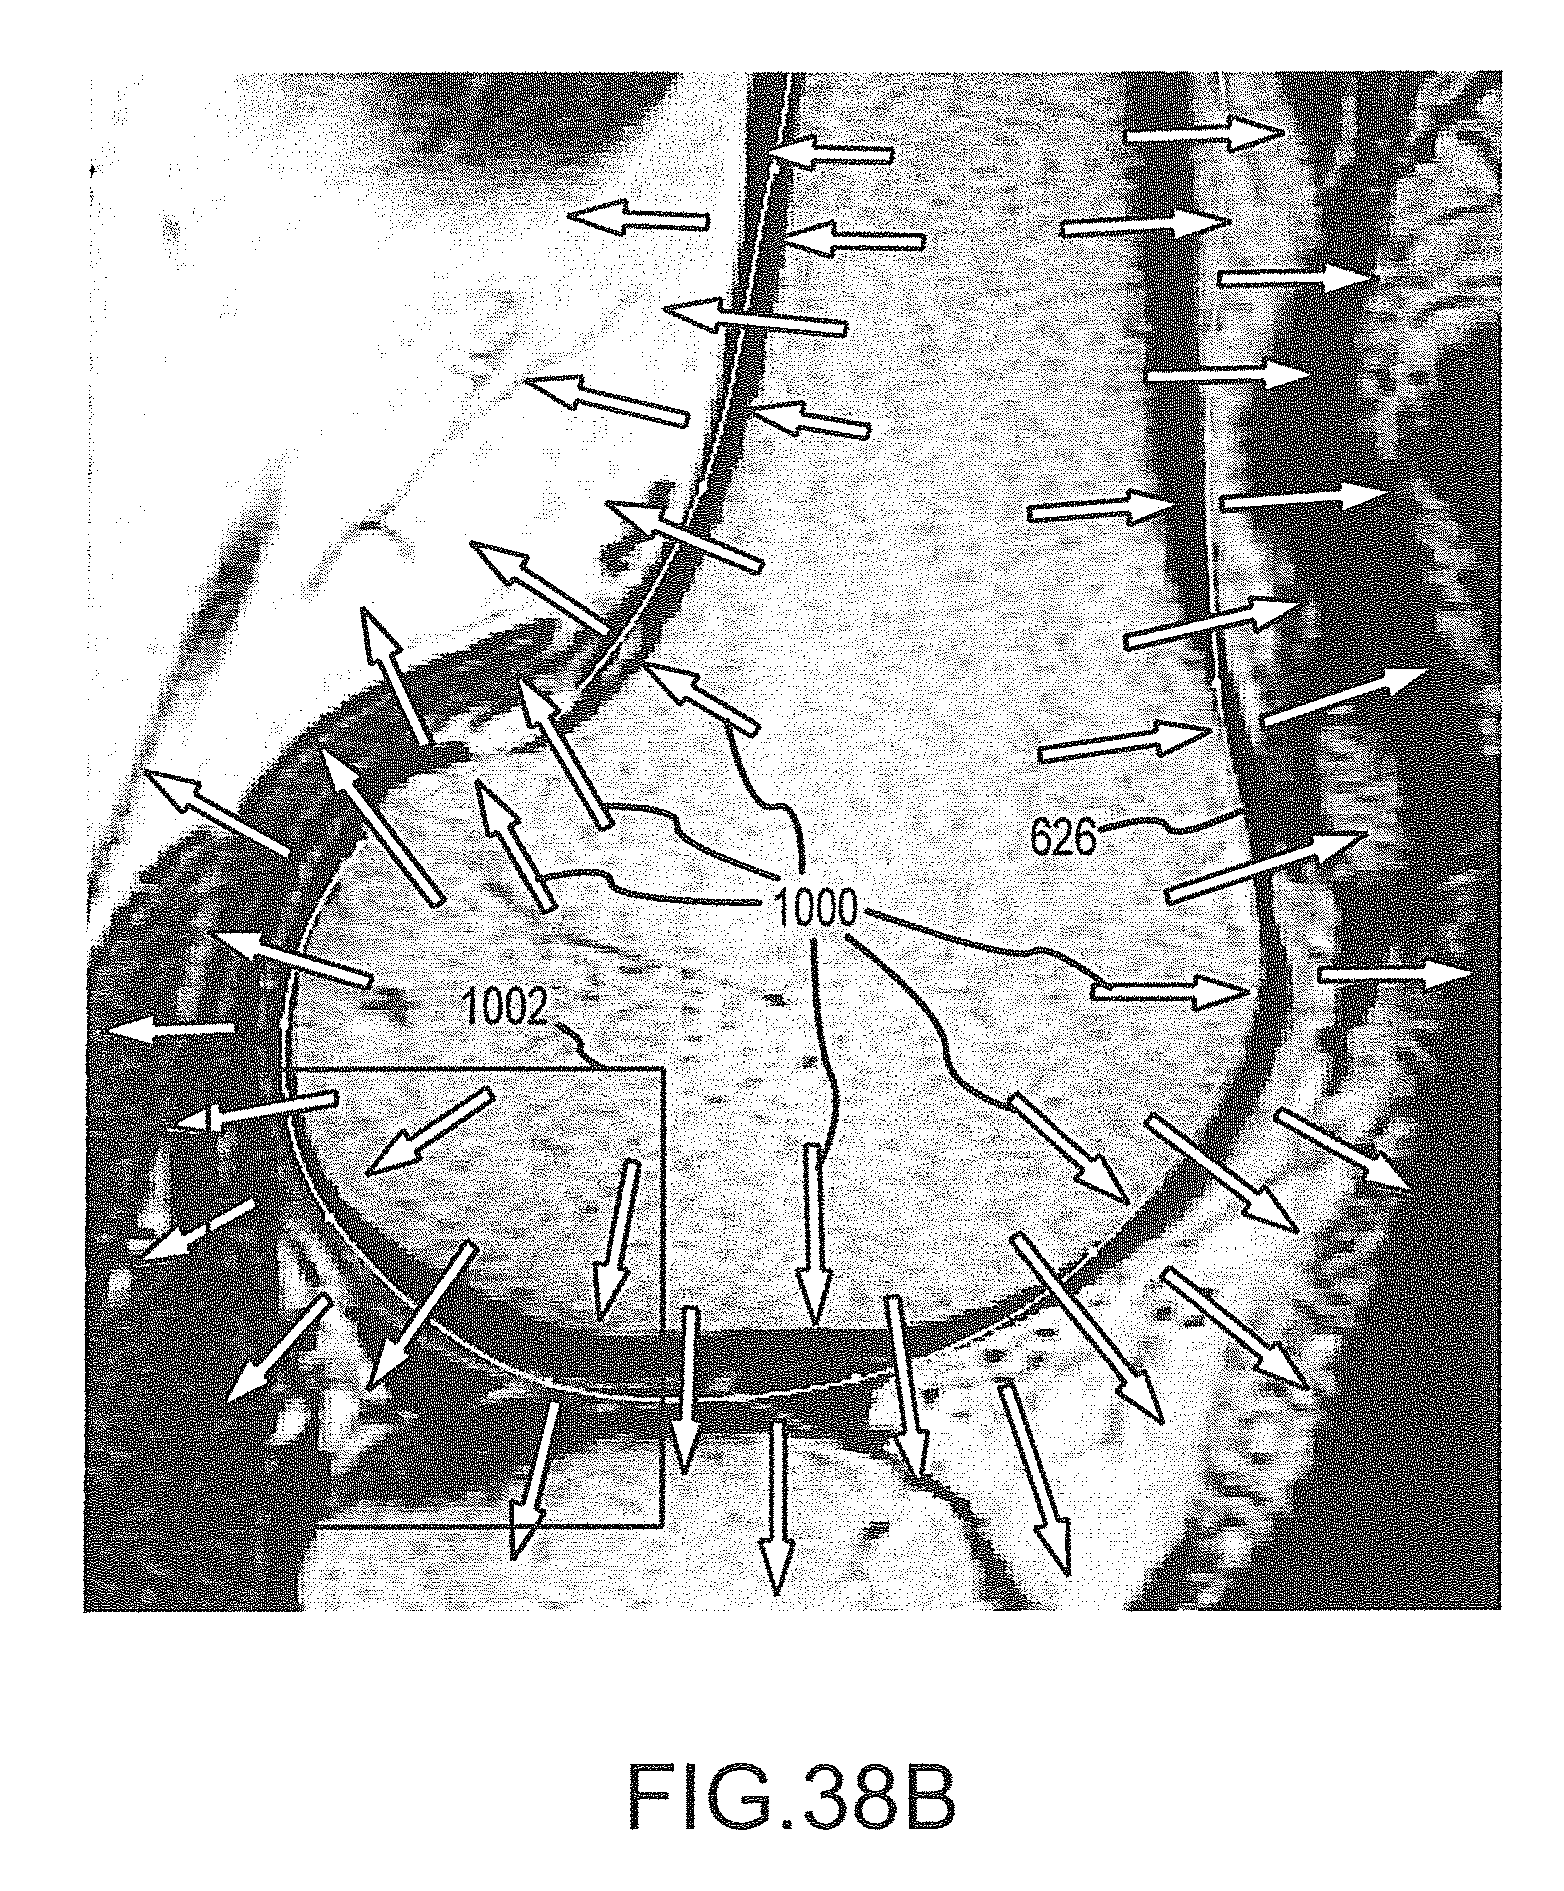

FIG. 38A is a flowchart illustrating the process of operation “Detect Appropriate Image Edges” of FIG. 37.

FIG. 38B is an image slice with a contour line representing the approximate segmentation mesh surface found in operation 770c of FIG. 37, the vectors showing the gradient of the signed distance for the contour.

FIG. 38C is an enlarged view of the area in FIG. 38B enclosed by the square 1002, the vectors showing the computed gradient of the target image.

FIG. 38D is the same view as FIG. 38C, except the vectors of FIGS. 38B and 38C are superimposed.